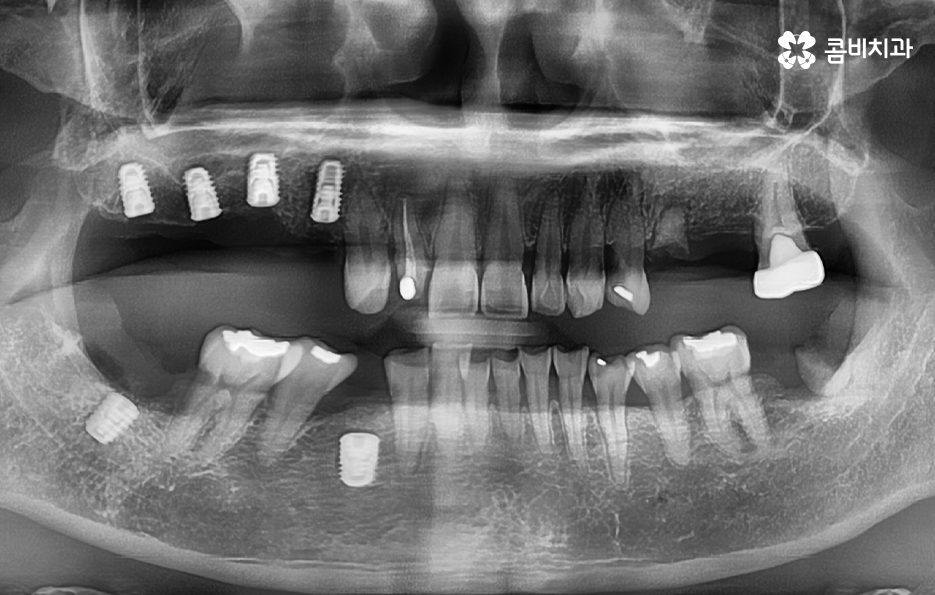

우리가 보편적으로 생각하게 되는 임플란트 치료기간의 경우 치아 하나를 상실하고 임플란트를 1:1로 치료할 때 예상 기간에 대해서 고려하게 되는 경우가 기본적인 접근 방법이라면 실질적으로 치과에서 임플란트를 하게 되는 연령대를 보더라도 보통 50대에서 60대 이후에 치아를 상실하게 되는 환자분들이 급증하기 때문에 위 사진의 사례처럼 여러 치아를 상실하고 임플란트를 식립하게 되는 경우도 많을 거예요

임플란트를 여러개 식립하면 더 오래 걸리나요?

물론 임플란트의 치료 계획에 따라 환자분들의 치료기간도 차이가 있겠지만 보편적으로는 임플란트를 여러개 식립한다고 해서 단순히 더 임플란트의 치료기간이 오래 걸리기 보다는 동시에 임플란트를 식립해도 임플란트 치료기간에서 중요한 골유착 기간은 비슷하기 때문에 식립 개수만큼 치료기간이 비례해서 늘어난다고는 볼 수는 없을 거예요

또는 식립 위치에 따라서 좌, 우 부분적으로 임플란트가 모두 필요한 경우 한 번에 모두 식립을 할 경우 식사가 제한이 되기 때문에 한 쪽 먼저 치료하고 반대쪽을 치료하는 경우가 많아 총 기간은 치료 계획에 따라 차이가 있을 수 있어요.